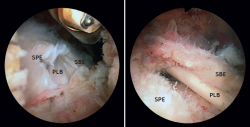

Se empleó la maniobra de palanca posterior del brazo, descrita por Burkhart(23), para mejorar el espacio anterior y permitir un mejor diagnóstico y acceso de la lesión (Figura 1). Esta se exploró desbridando inicialmente el intervalo rotador, como describe Lafosse(16), lo que permitió evaluar mejor la frecuente lesión de las paredes de la corredera de la PLB, la estabilidad de la PLB y el tamaño de la rotura del SBE y del SPE(23). Esta exploración se realiza desde el abordaje anterolateral subacromial, que permite una visión mucho más amplia, abarcando todo el espacio coracoides y el recorrido del tendón.

La exploración artroscópica permitió valorar las lesiones del SBE y del margen anterior del SPE de forma conjunta. Según se presentase esta asociación, se subclasificó como I-A y II-A a las roturas parciales aisladas del SBE y como tipos I-B y II-B a las parciales del SBE combinadas con roturas incompletas de la porción más anterior del SPE o roturas de patrón AS (Figura 2). Se trata de una subclasificación propia, que consideramos necesaria para una adecuada interpretación de los resultados de la reparación conjunta de ambos tendones, que requiere un abordaje diferenciado respecto a los de la reparación aislada del SBE.

Figura 3. Visión desde el portal subacromial posterior de roturas de tipos IB y IIB en hombros izquierdos. A: tipo IB; B: tipo IIB. PLB: porción larga del bíceps; SBE: subescapular; SPE: supraespinoso.